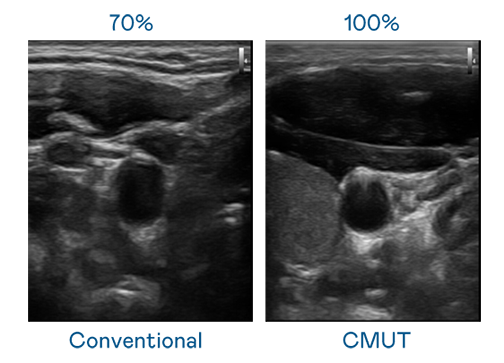

CMUT 技术是一种用电容式微机电元件来产生超音波讯号的技术。与传统 PZT 压电式技术相比,CMUT 频宽增加 30%,更宽频的超音波讯号让影像解析度大幅提升,是实现高影像品质医疗超音波扫描、促进精准医疗发展的关键技术。

大频宽带来超清晰影像

超音波影像的解析度高低,首先取决于探头能发出的讯号频宽。6686体育 CMUT 可提供高清晰的超音波讯号,提供高频宽、高灵敏度、影像纹理细节更高的超音波影像,协助医护人员缩短影像判读时间及利用精准的医疗影像进行诊断。